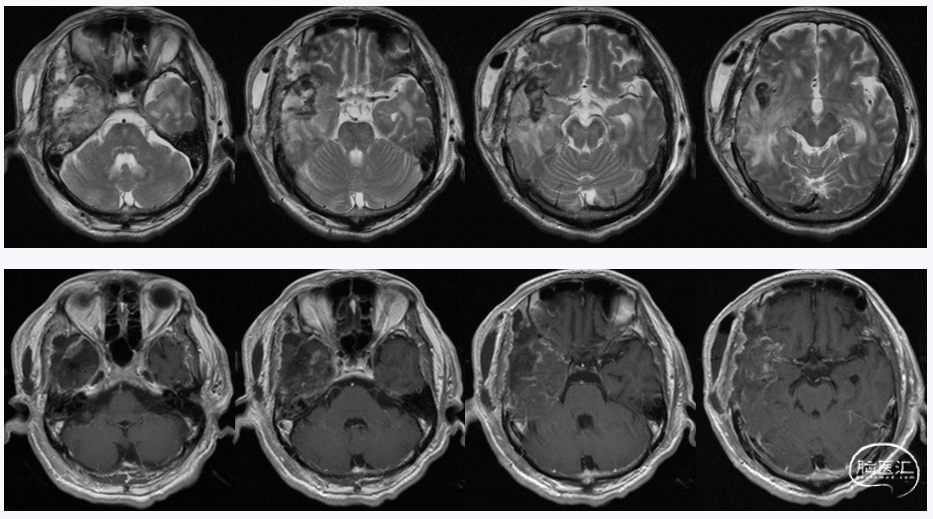

影像学检查